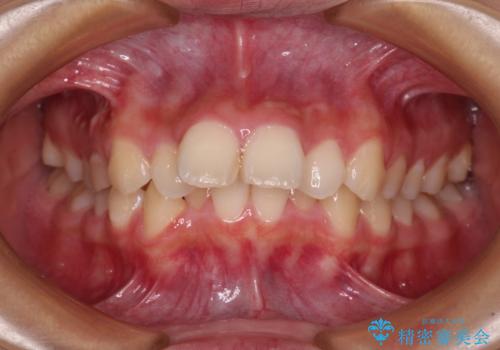

銀歯の下に虫歯 〈オールセラミッククラウン〉

担当医 瀧村怜未